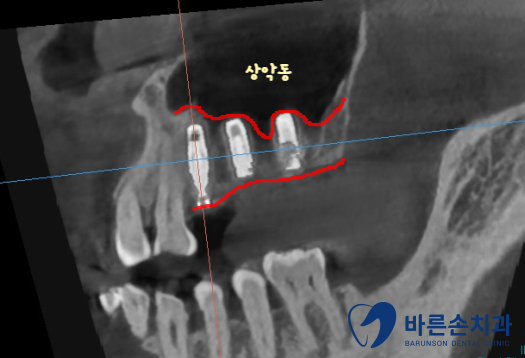

임플란트를 심기 위해서는 뼈가 충분히 있어야 하는데

상악동(빈 공간) 아래로 뼈가 너무 얇습니다.

상악동을 들어올려서 뼈이식을 충분히 하고 임플란트를 식립하기로 합니다.

이 수술 방법을 상악동 거상술이라고 해요.